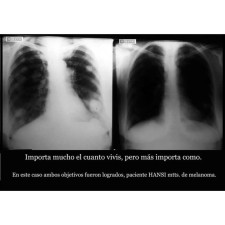

- Tratamientos para el dolor y enfermedades como el cáncer: Utilizan el método Hansi, un estimulante del sistema inmunológico que ha mostrado resultados satisfactorios en pacientes.